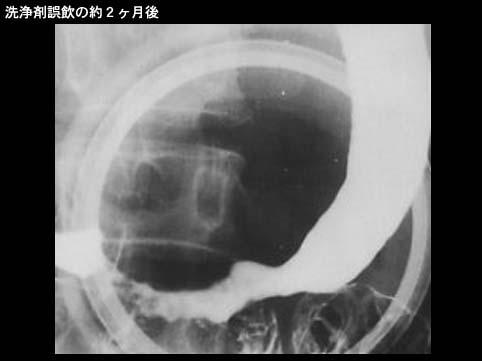

A case of corrosive gastritis due to the accidental ingestion of toilet cleaner.

Inflammatory or ulcerative disease / lesions/caustic (corrosive) gastritis

X-ray